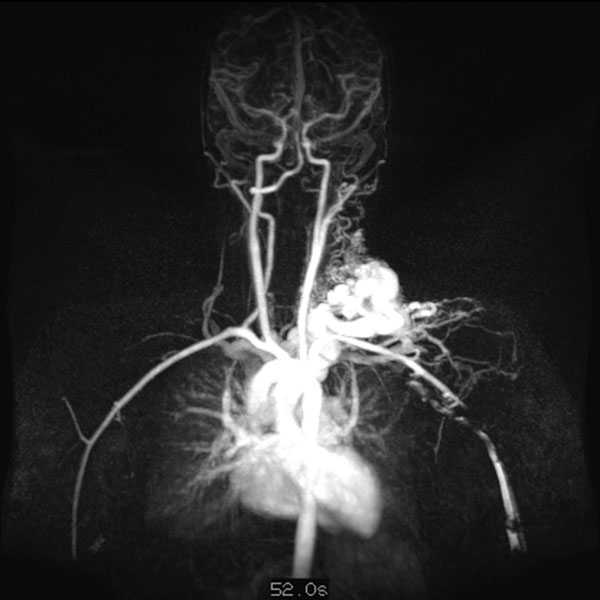

Dynamische, kontrastmittelunterstützte, zeitlich hochaufgelöste MR-Angiographie; Darstellung 52 s nach intravenöser Kontrastmittelapplikation. Bereits 5 s später fließt das Kontrastmittel sofort durch die arteriovenöse Malformation hindurch, eine Drainagevene ist ebenfalls bereits direkt kontrastiert. Typischer, extrem schneller Durchfluss einer arteriovenösen Malformation als Fast-flow-Läsion.